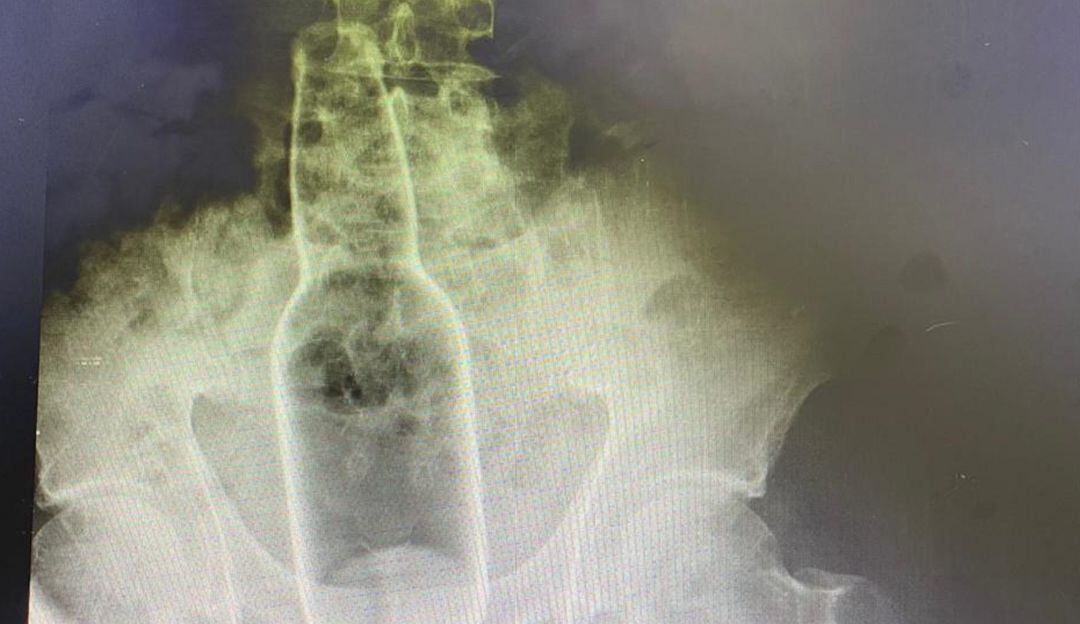

Radiografía del cuerpo extraño introducido en el recto del extranjero. / Cortesía Caracol Radio

El sujeto, de aproximadamente 50 años de edad, tuvo que ser intervenido tras introducirse una botella de cerveza. Al parecer, esta práctica se realizó con el consentimiento de la esposa del hombre, quien, llevada por un placer inimaginable, le penetró el objeto que finalmente fue extraído por especialistas de un centro médico de la ciudad.